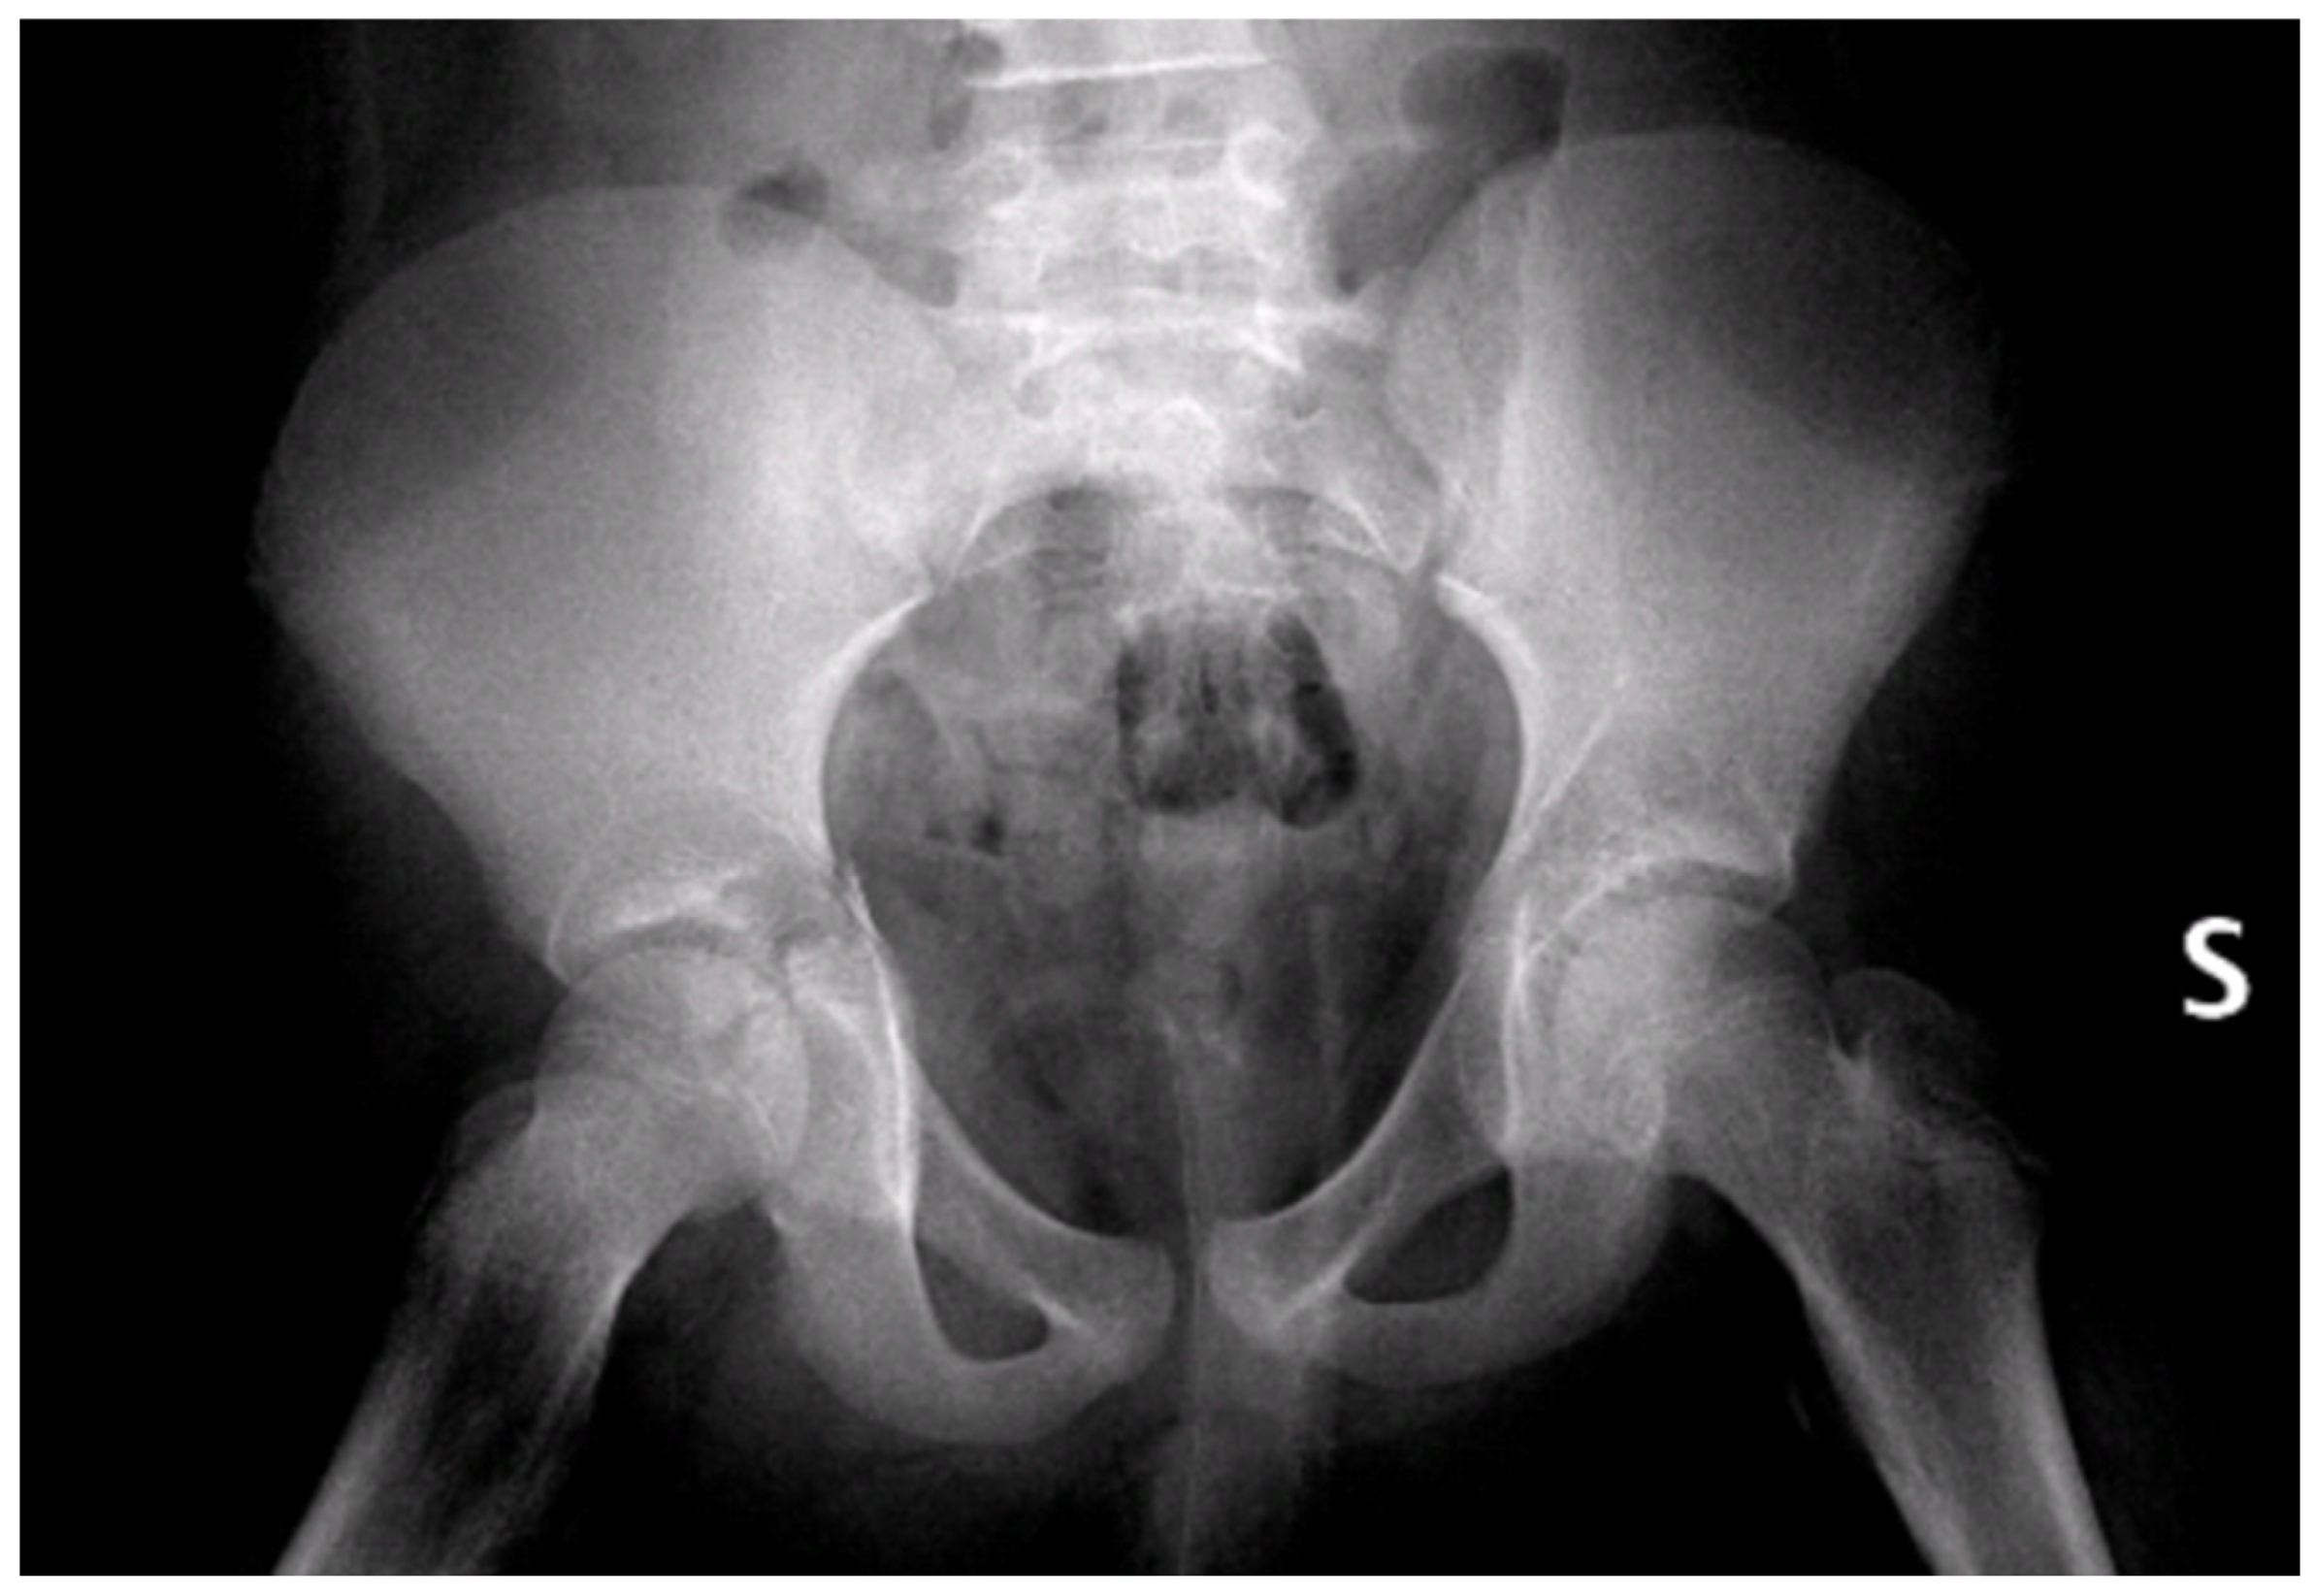

Initial radiographs (Figure 2) and CT imaging revealed an open fracture of the right tibia with involvement of the tibial plateau (Schatzker IV) and a vertical fracture line extending below the tibial tuberosity; a transverse fracture of the right acetabulum with disarticulation of the triradiate cartilage (Figure 3); a suspected fracture at the level of the left lesser trochanter; bilateral pulmonary contusions (segments of the upper and lower lobes); a thin parafalcine and paratentorial intracranial haemorrhage without mass effect; no craniofacial or cervical spine fractures; no solid-organ injury in the abdomen; a small simple cyst in the left kidney; and developmental changes in thoracic vertebral bodies (D6–D8) without acute traumatic lesions. The patient was haemodynamically stable after initial resuscitation. Neurovascular examination of the lower limbs was normal at presentation.

Figure 2.

Pelvic X-rays at admission time. S = left side.